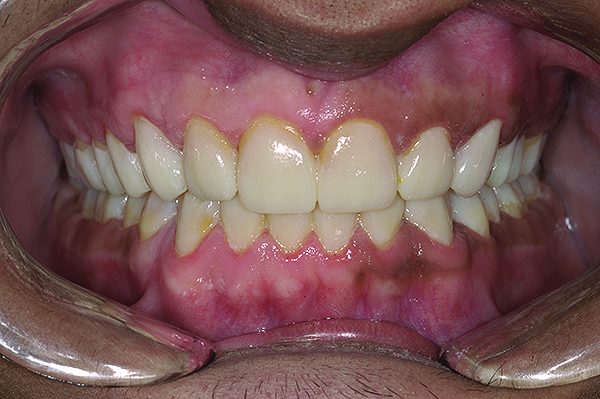

Figure 2. Preoperative 1:2 retracted frontal view.

Figure 2

The authors report on a 21-year-old patient who presented with severe discoloration and mild sensitivity of teeth (Figure 1). The teeth visible in his smile were very short, unsightly, and unbecoming for his age.

A thorough clinical examination and analysis were carried out to assess the esthetic and functional problems of the patient (Figure 2 through Figure 7). The medical history was non-contributory, except for mild leukoderma. Temporomandibular joint (TMJ) function was within normal range.

Mounted study casts were used to evaluate occlusion. The relevant findings were as follows2: Facial analysis revealed a canted maxillary occlusal plane and canted dental midline. Dentolabial analysis showed that the maxillary incisors were not adequately visible during repose; it also revealed a reverse smile line, as well as a wide smile showing 12 teeth. Results from the phonetic analysis were that “F” and “V” sounds revealed upper incisal shortening, “M” and “S” pronunciation disclosed a diminished vertical dimension of occlusion (VDO), and “E” sounds showed severe shortening of incisors. Dental analysis revealed thick biotype, asymmetry and inappropriate location of gingival levels and zenith, incorrect axial inclinations, a displeasing width-to-length ratio, and pitted surfaces on most teeth. Interproximal decay was evident on several posterior teeth, as revealed by radiographic analysis. Finally, occlusal examination indicated discrepancy between maximum intercuspation (MIP) and centric relation (CR) as well as a lack of anterior guidance/posterior disclusion.